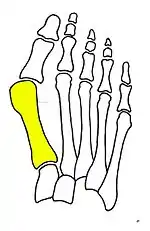

Primus varus deformity

Primus varus deformity is the leaning of the first metatarsal bone away from the second metatarsal and towards the opposite foot (Fig. 1). As it leans over, its head sticks out to form the bunion bump and it also widens the forefoot to cause shoes feeling too tight. Thus when bunion pain becomes unmanageable, surgical correction is to narrow the forefoot by repositioning of the first metatarsal head back to its normal position. This can be done by osteotomy (bone-breaking), soft tissue (non-osteotomy) or fusion techniques.

Syndesmosis procedure addresses specifically the two fundamental problems of metatarsus primus varus deformity that gives rise to the bunion deformity. They are leaning and instability of the first metatarsal bone . Syndesmosis procedure uprights the leaning first metatarsal bone with strong binding sutures between it and the second metatarsal bone (Fig. 2) and then also stabilizes it uniquely by creating a fibrous connecting bridge between these two bones (Fig. 3, 4). First metatarsal bone can be readily realigned because by definition of the metatarsus primus varus deformity its first metatarsal is abnormally loose and mobile.